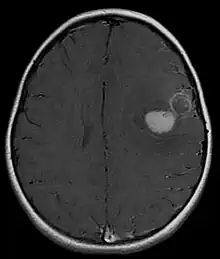

Supratentorial central PNET in a 5-year-old patient

PNET of the CNS generally refer to supratentorial PNETs.